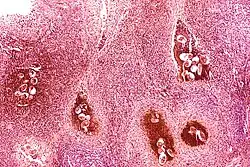

Certain bacterial infections also increase the risk of cancer, as seen in Helicobacter pylori-induced gastric carcinoma.[79] The mechanism by which H. pylori causes cancer may involve chronic inflammation or the direct action of some of the bacteria's virulence factors.[80] Parasitic infections strongly associated with cancer include Schistosoma haematobium (squamous cell carcinoma of the bladder) and the liver flukes, Opisthorchis viverrini and Clonorchis sinensis (cholangiocarcinoma).[81] Inflammation triggered by the worm's eggs appears to be the cancer-causing mechanism. Certain parasitic infections can also increase the presence of carcinogenic compounds in the body, leading to the development of cancers.[82] Tuberculosis infection, caused by the mycobacterium M. tuberculosis, has also been linked with the development of lung cancer.[83]

There is evidence that inflammation itself plays an important role in the development and progression of cancer.[84] Chronic inflammation can lead to DNA damage over time and the accumulation of random genetic alterations in cancer cells.[85] Inflammation can contribute to proliferation, survival, angiogenesis and migration of cancer cells by influencing tumor microenvironment.[86] Individuals with inflammatory bowel disease are at increased risk of developing colorectal cancers.[13]